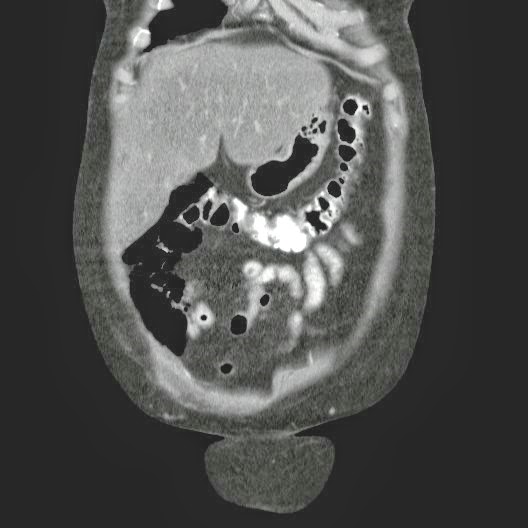

- ¿Hallazgos Escanografia?

2. Hay una colección de la pared abdominal en el flanco derecho, que realza en la periferia con el contraste, e intraabdominal tiene aire pero no me parece colección intraabdominal porque la grasa no está alterada.